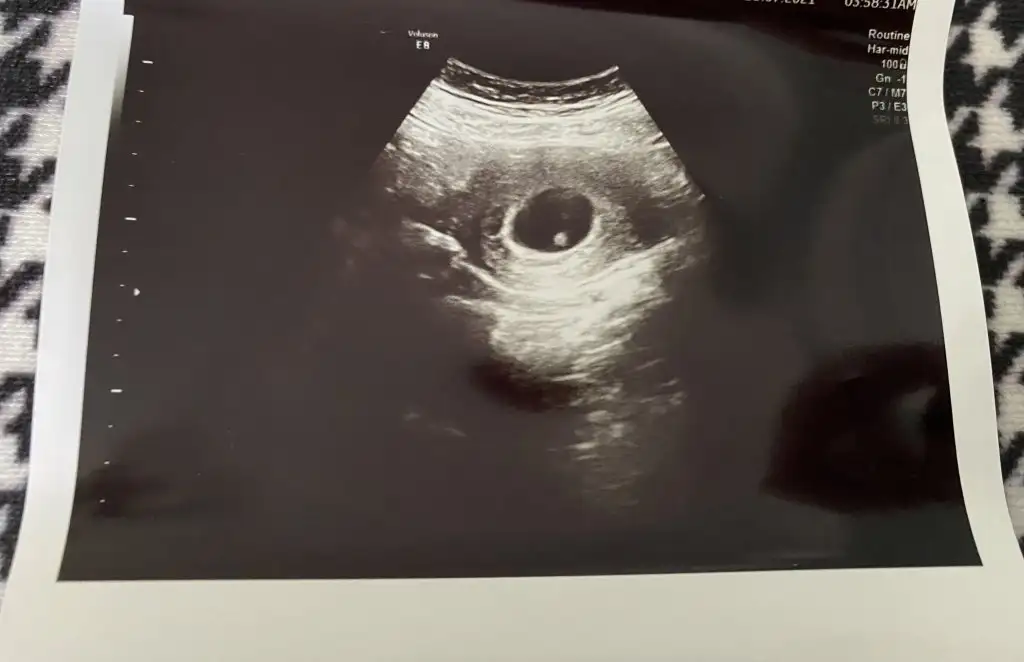

Erkekvajinal ultrasonla bakıldı. 5 +5 haftalık.sizce cinsiyet ne